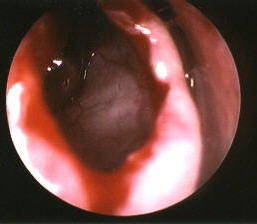

| This picture was taken during a typical case. The patient presented with acute exacerbations of chronic rhinosinusitis. The picture illustrates an opening into a concha bullosa, or a sinus within the middle turbinate, on the patient's right side. The lateral wall of this sinus will be removed to provide drainage for this sinus, and improve the drainage pathways for the other surrounding sinuses. There is always some bleeding, but with good vasoconstriction it is not too voluminous. This patient went on to heal very nicely and felt "a hundred times better." | ||||||||||||||||||||